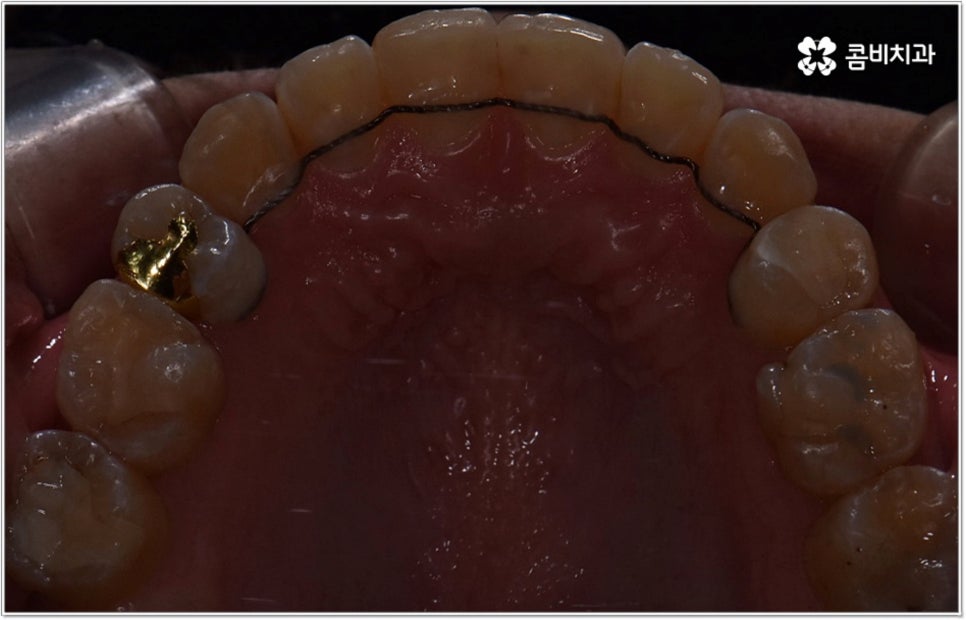

잘 아시다시피 교정이란 치아에 교정 장치 (브라켓) 를 부착하고 와이어에 교정력을 걸어 필요한 방향으로 치아를 이동시킴으로써 고른 치열과 올바른 교합을 가진 정상적인 구강 구조를 회복하는 치과 진료를 의미하는데요, 말씀드린 것처럼 부정교합에는 다양한 형태가 있고 또한 환자분들마다 심각한 정도가 모두 다르기 때문에 현 상태를 면밀하게 체크하고 맞춤 교정 치료 계획을 세우는 것이 무엇보다 중요하다고 할 수 있습니다. 즉 3D CT 와 같은 정밀 진단 장비를 갖추고 있는 치과에서 교정 관련 임상 경험이 풍부한 숙련된 의료진과 함께 치료를 진행하는 것이 필수적이라고 할 수 있어요. 전체 방향 및 세부 플랜을 세울 때 각 환자에 맞게 치아의 이동 속도에 무리가 가지 않도록 하기 위해서 연령이나 발달 상황, 진행 상황을 면밀하게 살펴보는 것이 필요하며 또한 구강 내 공간 유무 및 부정교합 정도에 따라 발치 또는 비발치치아교정 여부를 결정하게 될 거예요.

만약 치아가 이동할 범위를 계산해 봤을 때 공간이 충분하다면 굳이 치아를 뽑지 않고 비발치치아교정 과정으로 치료할 수 있어요. 제일 뒤에 있는 어금니를 더 후방으로 이동시키거나 치간 삭제, 악궁확장장치 등으로 치아 사이를 벌려서 이동 공간을 확보할 수 있으면 비발치치아교정 이 가능한 거예요. 이 때 부정교합이 심각하거나 악골이 치아에 비해 많이 작은 경우, 구조적인 원인을 개선할 필요성이 있는 경우 등 발치 교정을 하는 것이 꼭 필요한 케이스라면 치아를 뽑아주어야 하며, 환자분들의 상황에 따라 다르지만 보통은 소구치를 발치하는 경우가 많이 있습니다.